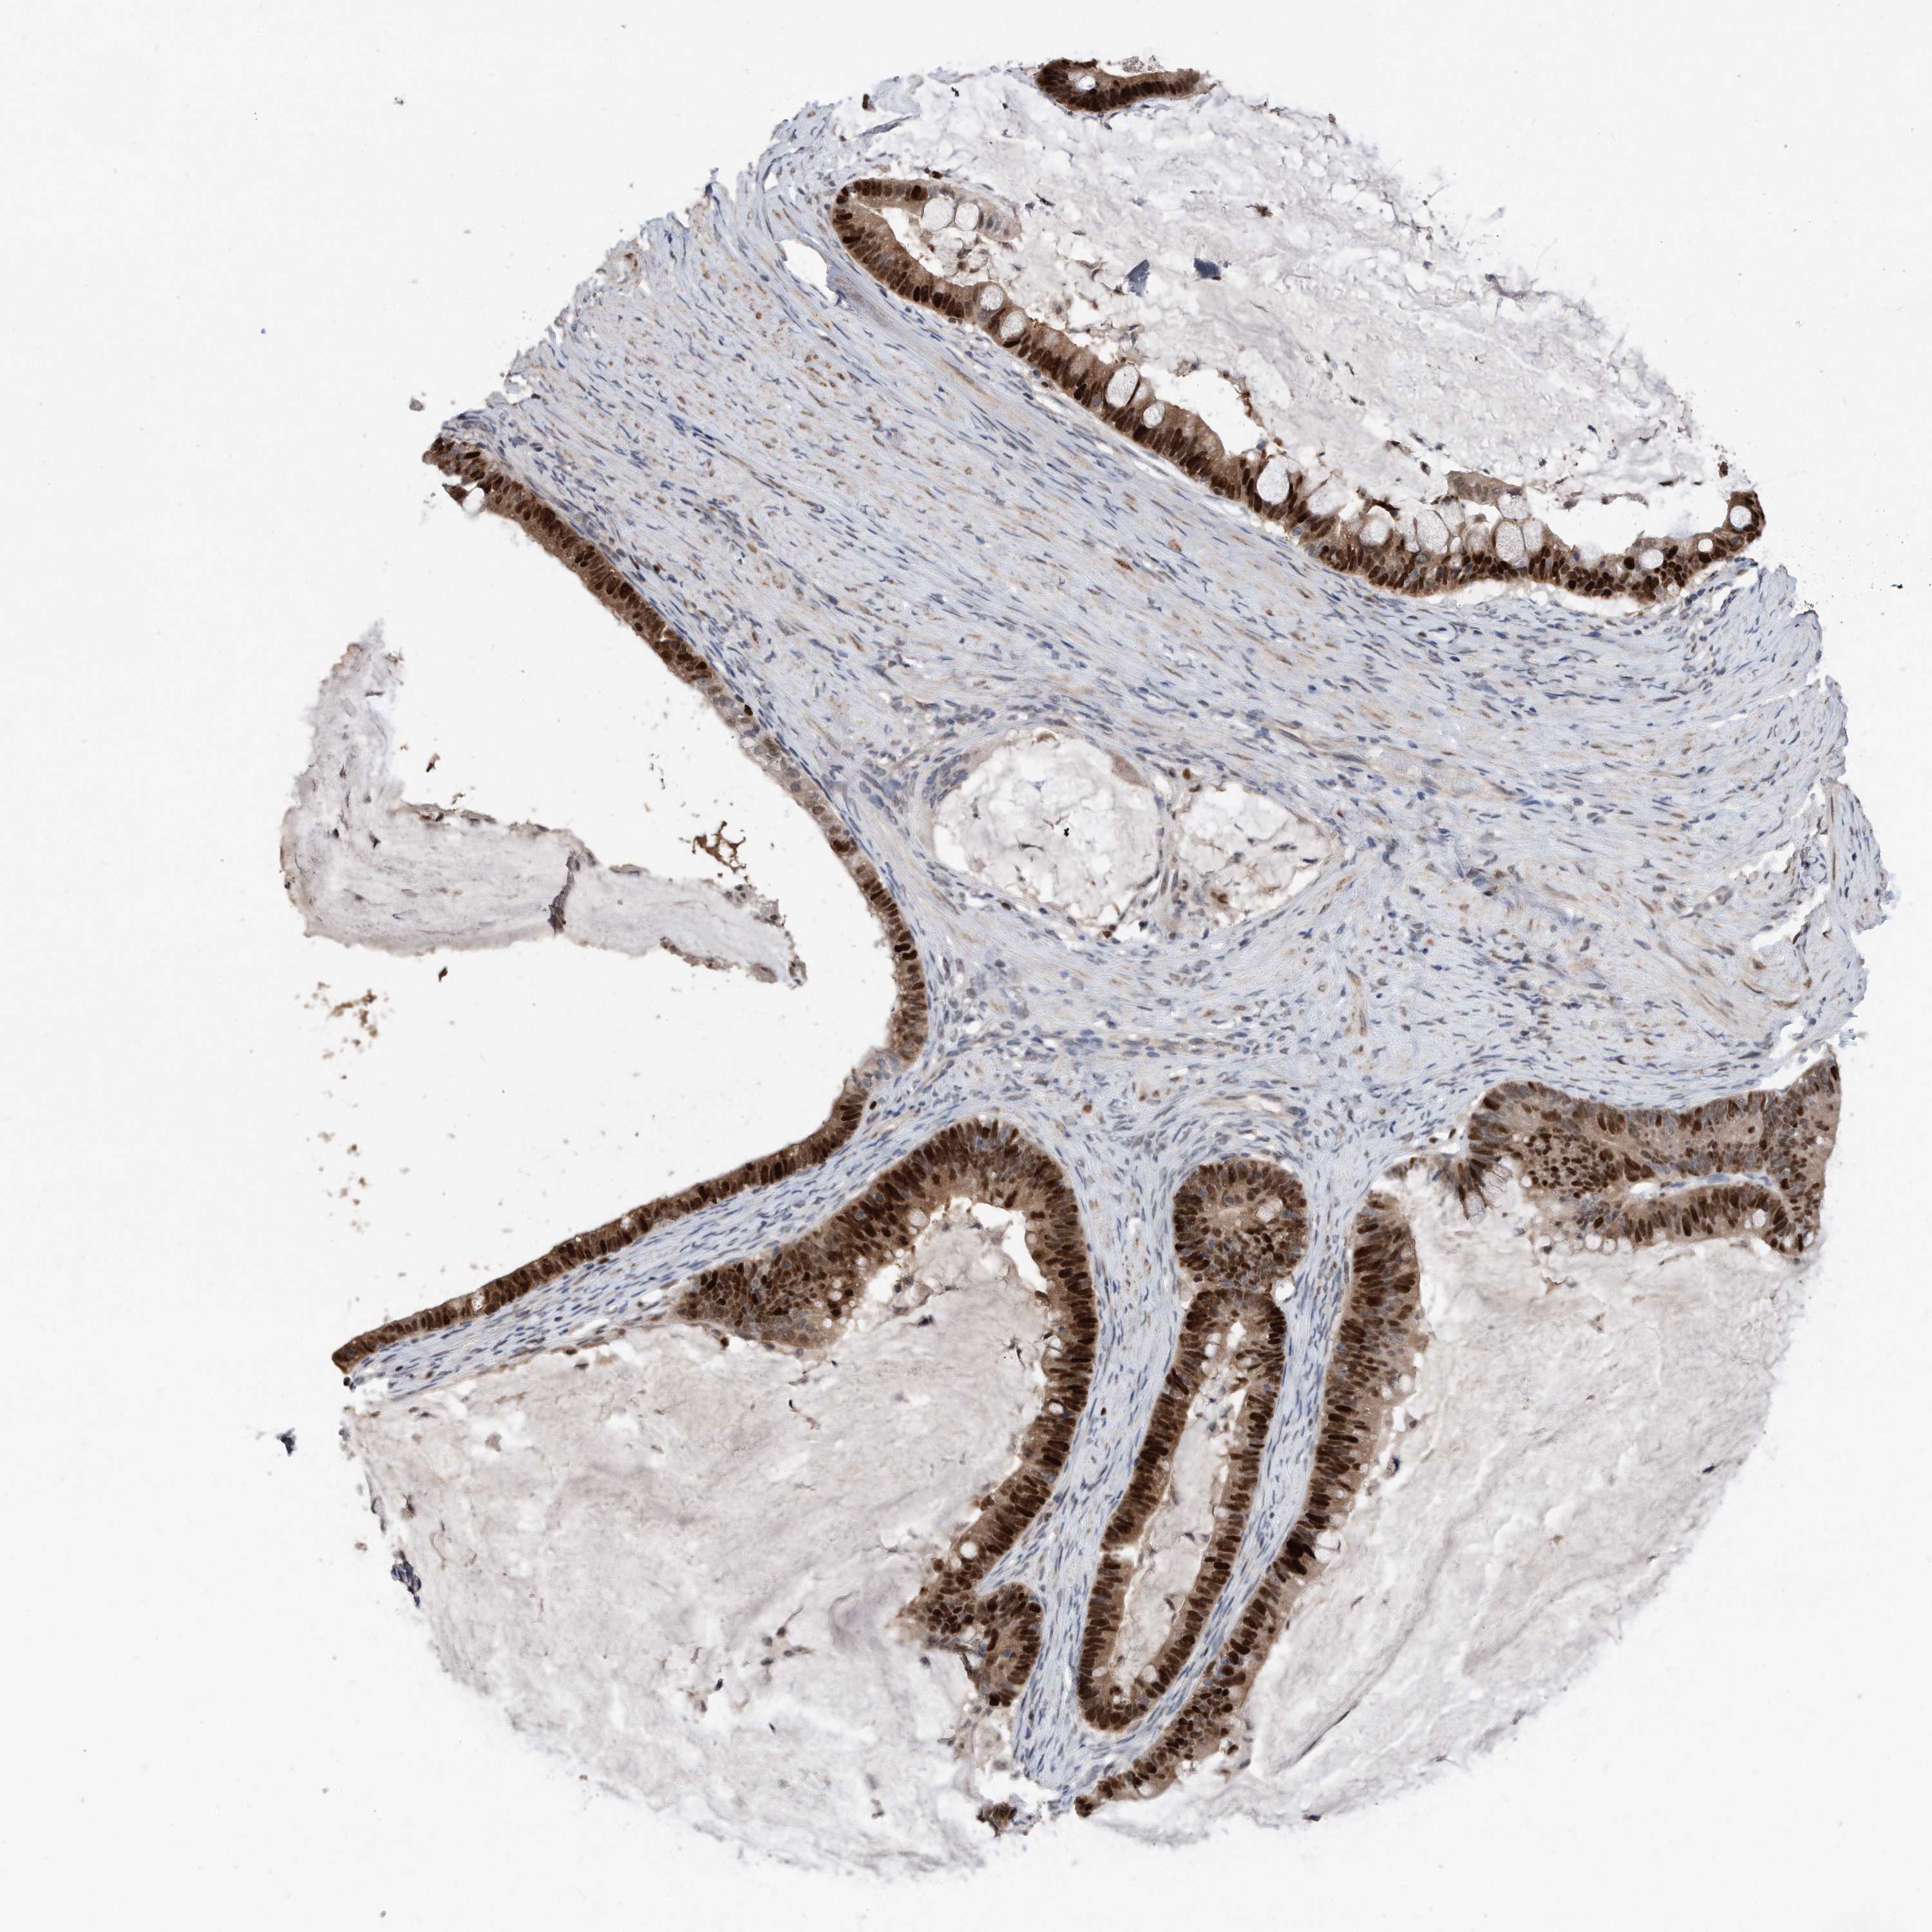

OVARIAN CANCER - Protein expressioni

A mouse-over function shows sample information and annotation data. Click on an image to view it in a full screen mode. Samples can be filtered based on level of antibody staining by selecting one or several of the following categories: high, medium, low and not detected. The assay and annotation is described here.

Note that samples used for immunohistochemistry by the Human Protein Atlas do not correspond to samples in the TCGA dataset.

Antibody stainingi

Antibody staining in the annotated cell types in the current human tissue is reported as not detected, low, medium, or high, based on conventional immunohistochemistry profiling in selected tissues. This score is based on the combination of the staining intensity and fraction of stained cells.

Each image is clickable and will lead to virtual microscopy that enables deeper exploration of all samples and also displays staining intensity scores, fraction scores and subcellular localization as well as patient and tissue information for each sample.

HPA030521

HPA030522

HPA030523

CAB000148

CAB080240

CAB080241

CAB080242

Staining

High

Medium

Low

Not detected

Intensity

Strong

Moderate

Weak

Negative

Quantity

>75%

75%-25%

<25%

None

Location

Nuclear

Cytoplasmic/membranous

Cytoplasmic/membranous,nuclear

Cystadenocarcinoma, serous, NOS

Carcinoma, endometroid

Cystadenocarcinoma, mucinous, NOS

Carcinoma, NOS